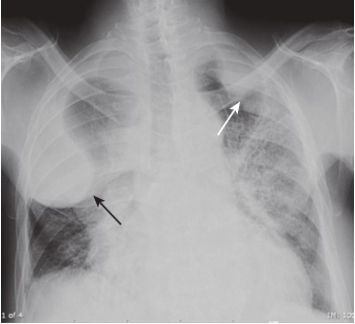

Loculated pleural effusions.

There are bilateral fluid collections (white and black arrows) that have unusual shapes and seem to defy gravity, because they are trapped in the pleural space, usually by adhesions. Loculated effusions can be suspected when an effusion has something other than a meniscoid shape or collects in a location other than the base of the lung (e.g., if the effusion were to remain at the apex of the hemithorax even if the patient were upright).